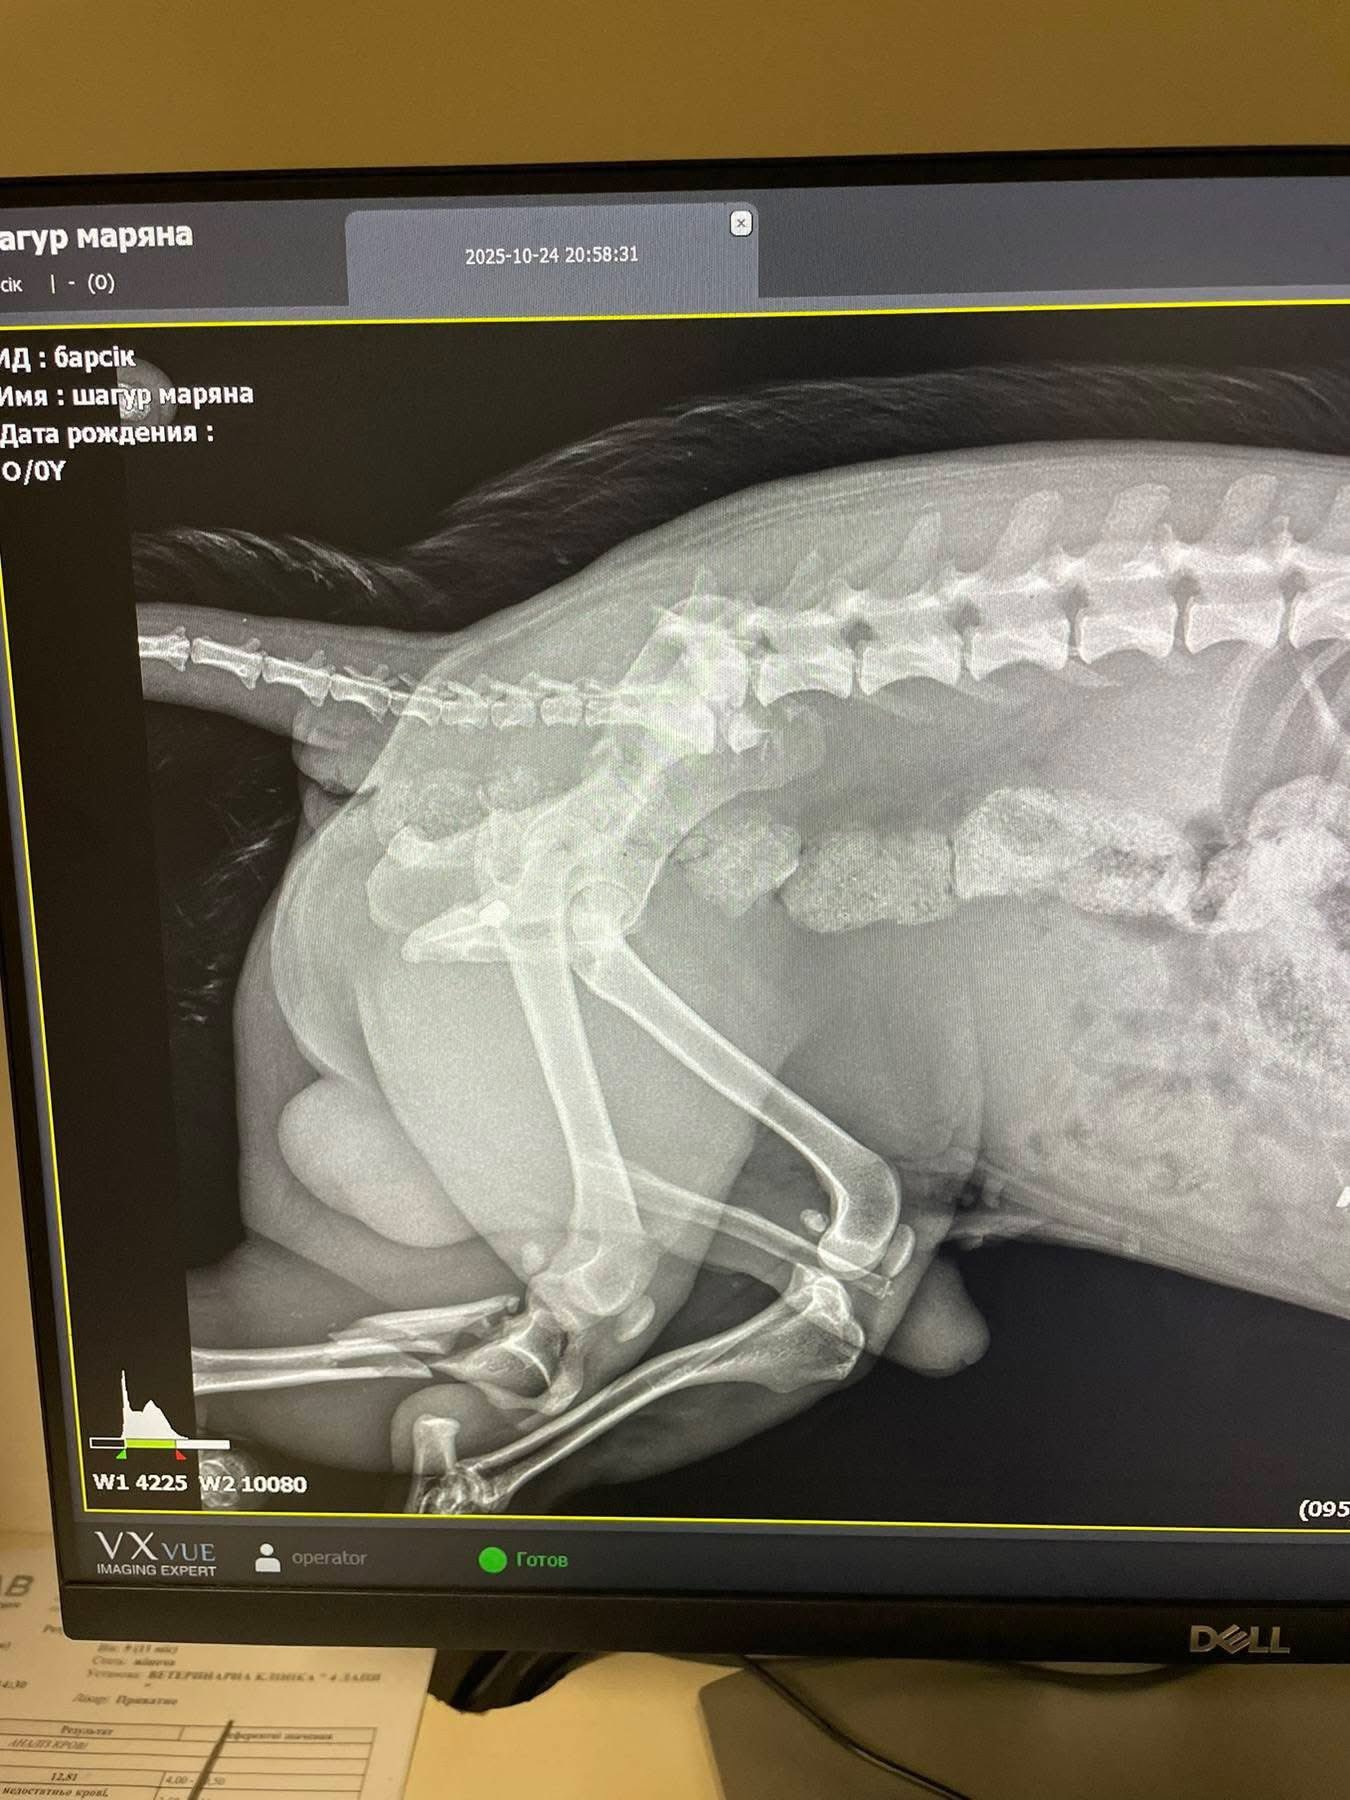

Як зазначено в дописі, огляд та рентген показали наявність у тілі тварини двох куль. Окрім цього, у собаки роздроблені кістки на лапі.